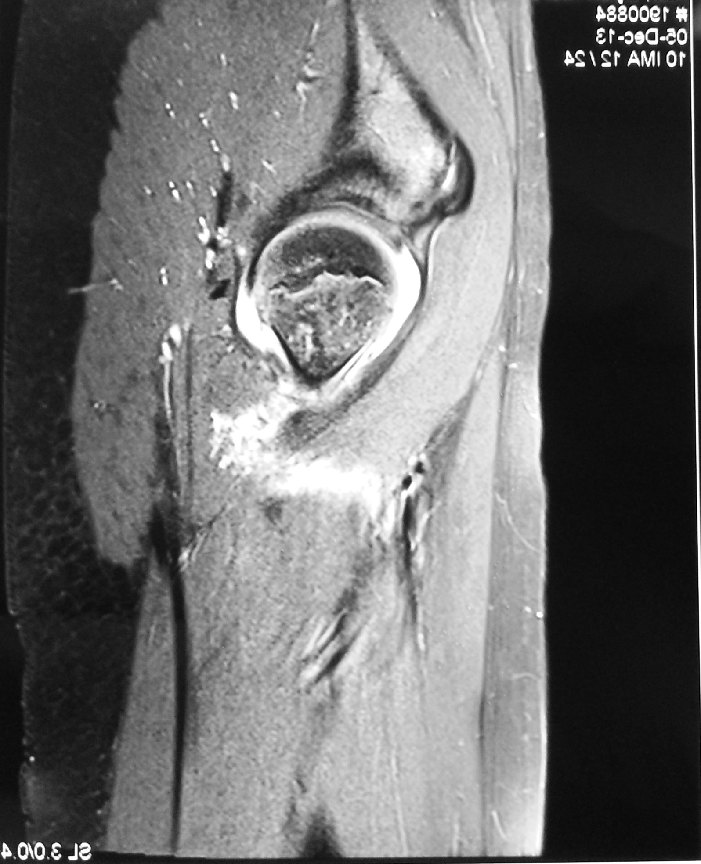

An ultrasound scan or an MRI scan of the hip joint can be done.

The fluid obtained from the hip joint showed pus.

The hip joint as viewed using the arthroscopic camera: